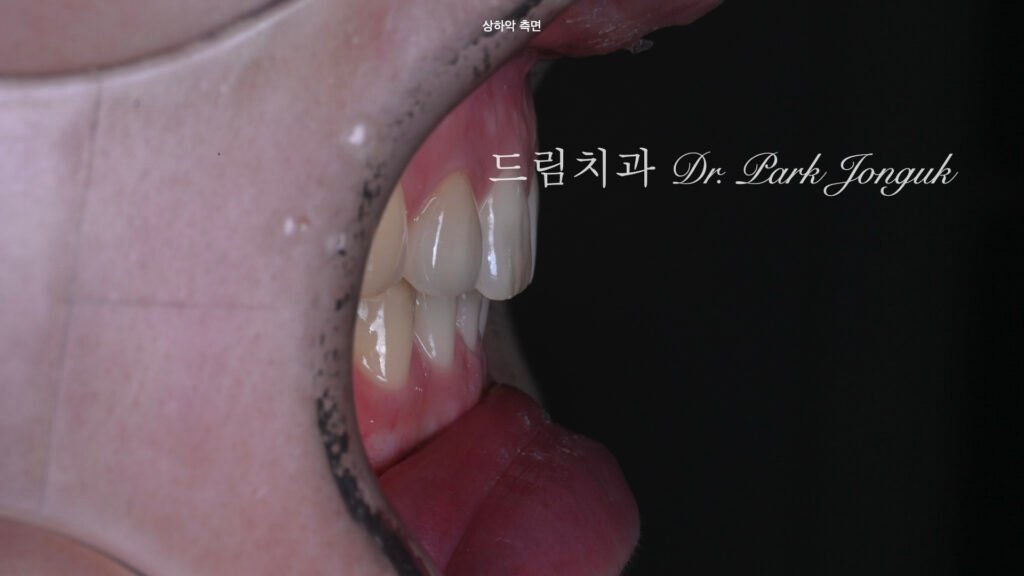

5. 결과: 밝고 조화로운 미소의 완성 (사진 8~10)

[사진 8, 9, 10 참조] 시술 후의 모습은 어느 것이 크라운이고 어느 것이 무삭제 라미네이트인지 구분하기 힘들 정도로 완벽한 일체감을 보여줍니다.

- Shade Harmony: 전체적으로 밝고 맑은 톤으로 치아 색상이 개선되었습니다.

- Profile Improvement: 옥니가 개선되어 전방 볼륨감이 생겼으며, 웃을 때 치아 노출량이 증가하여 훨씬 젊고 활기찬 인상을 줍니다.